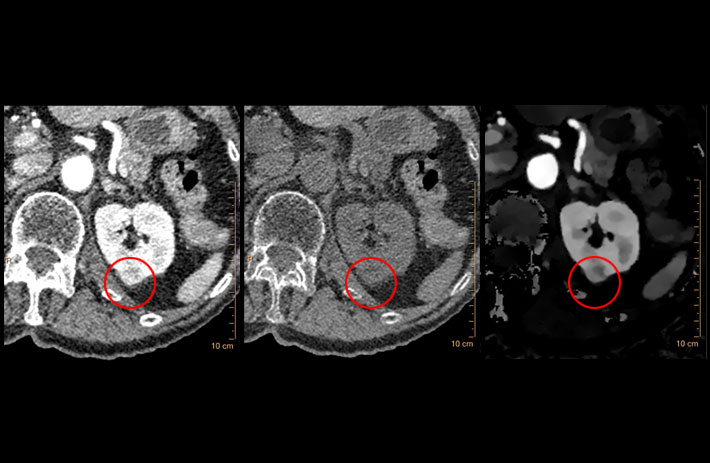

Mit dem Spektral-Detektor-CT werden Spektraldaten automatisch bei jedem Scan erfasst. Die Informationen stehen jederzeit auf der Scankonsole, der CT-Workstation sowie an jedem PACS-Arbeitsplatz zur Verfügung, sodass es nicht notwendig ist, den Patienten erneut zu scannen, bspw. wenn initial zufällige Anomalien festgestellt wurden. Dadurch profitieren Anwender durch eine höhere Diagnosesicherheit und weniger Nachuntersuchungen auf anderen bildgebenden Systemen. Unsere Fallsammlung zeigt, welchen klinischen Mehrwert der Spektral-Detektor-CT in unterschiedlichsten Anwendungsbereichen in der klinischen Routine bringt. Jede Woche gehen neue Fälle live.